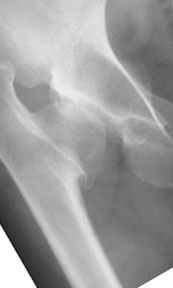

It appears that this patient has bilateral congenital hip displasia, as presented on the radiographs. As shown, the problem involves both sides of the hip joint: the acetabulum and proximal femur.

In this patient, it appears that addressing either the femur or the acetabulum will be insufficient to help correct this patient’s problem. It would be necessary to approach both sides of the hip joint to correct the hip dysplasia.

Depending upon surgeon preference, as well as availability of adequate operating room equipment and staff, this reconstruction can be done in two stages: periacetabular osteotomy with correction of acetabular retroversion would be the first stage. The second stage would involve a proximal femoral valgus osteotomy with neck lengthening.

In this second stage, a 120 degree blade plate can be used for correction proximal femur varus deformity. These procedures are both technically difficult, and require a great amount of pre-operative planning, both by the surgeons involved as well as the operating room staff.

The pre-operative planning would need to be done with the use of more radiographs for assessment of the hip dysplasia. These x-rays include a repeat AP pelvis, separate AP and lateral of the hips, long-standing femoral axis views of both legs, false profile view, as well as abduction and adduction films.

Pic. 1-5 preop plan; 6-8 similar case